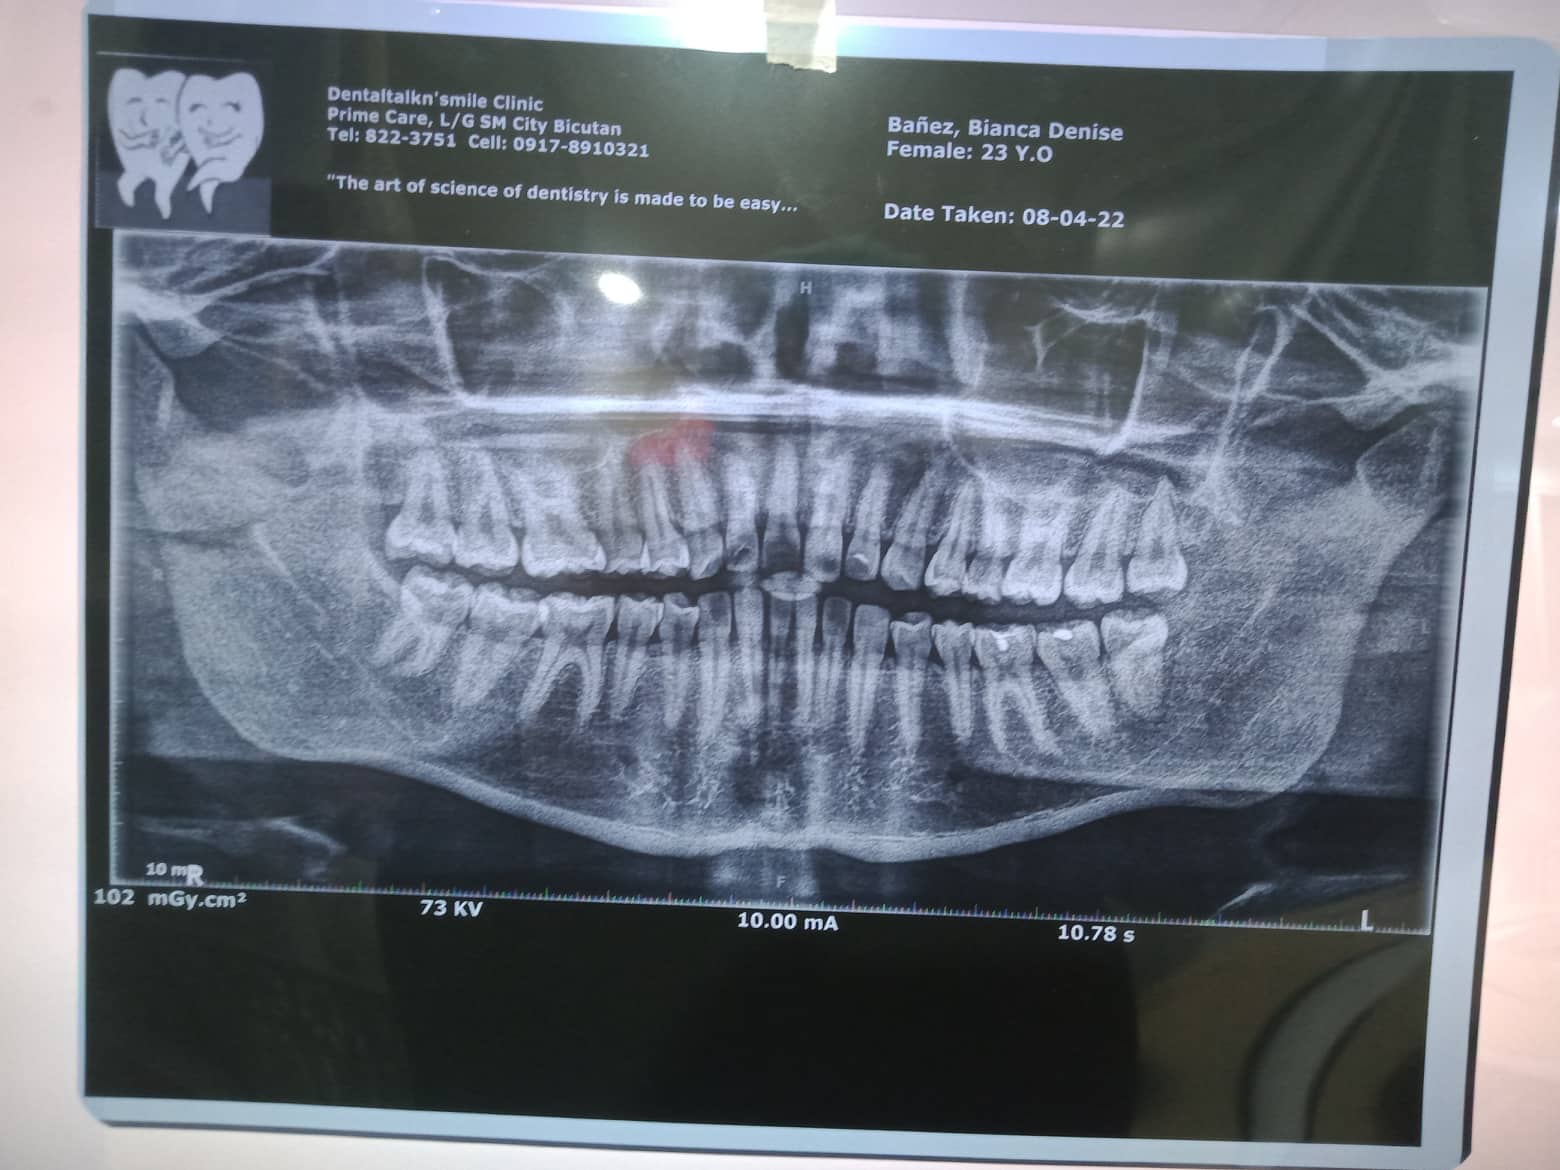

Edit Record Check our patient data records. Add patient information Patient Info Profile picture Last Name First Name Middle Name Birthdate Age Street Barangay City Country Zip Code Contact number Email Procedure 8/9/10=- intallation , 14 NITI U/L , roth 0.22 , w/ occlusal pads #36&46 *Ceph & Panoramic 9/6/22 - U/L SAME WIRE; Reattach # 45, #16BT 10/19/22- u 16 nITI/ 16 SSl/ CHAIN 42-32/ REATTACH #12 01/28/23- same wire 11/19/22- adj 12/28/22- ADJ/1 REATTACHED 1/27/23- adj 03/04/23- reverse curved L / penguin box #14-15-#43-44, #24-25-#33-34/ reattached #16,26,36 06/27/23- 08/02/23- same wire/ U double wire 16 ss extrude monkey elastic 13-23-43-33 01-06-24 ADJ 3 reattachment #43, 44, 45 RC 18 NiTi 05/18/24 Adj ***next meeting for #43,45,34,35 06/12/24 Adj 18 NITI U/L new bracket 43.45,34,35 07/30/24 Adj same wire reattached #11,21,45,34 File 303563691_1753655458304251_7294591679368448177_n_1.jpg File 2 302283051_758200575249092_1452457400021526470_n.jpg File 3 File 4 File 5 File 6 File 7 File 8 File 9 File 10 File 11 File 12 File 13 File 14 File 15 File 16 File 17 File 18 File 19 File 20 Retain Record Retain Record Yes No Save Your Changes